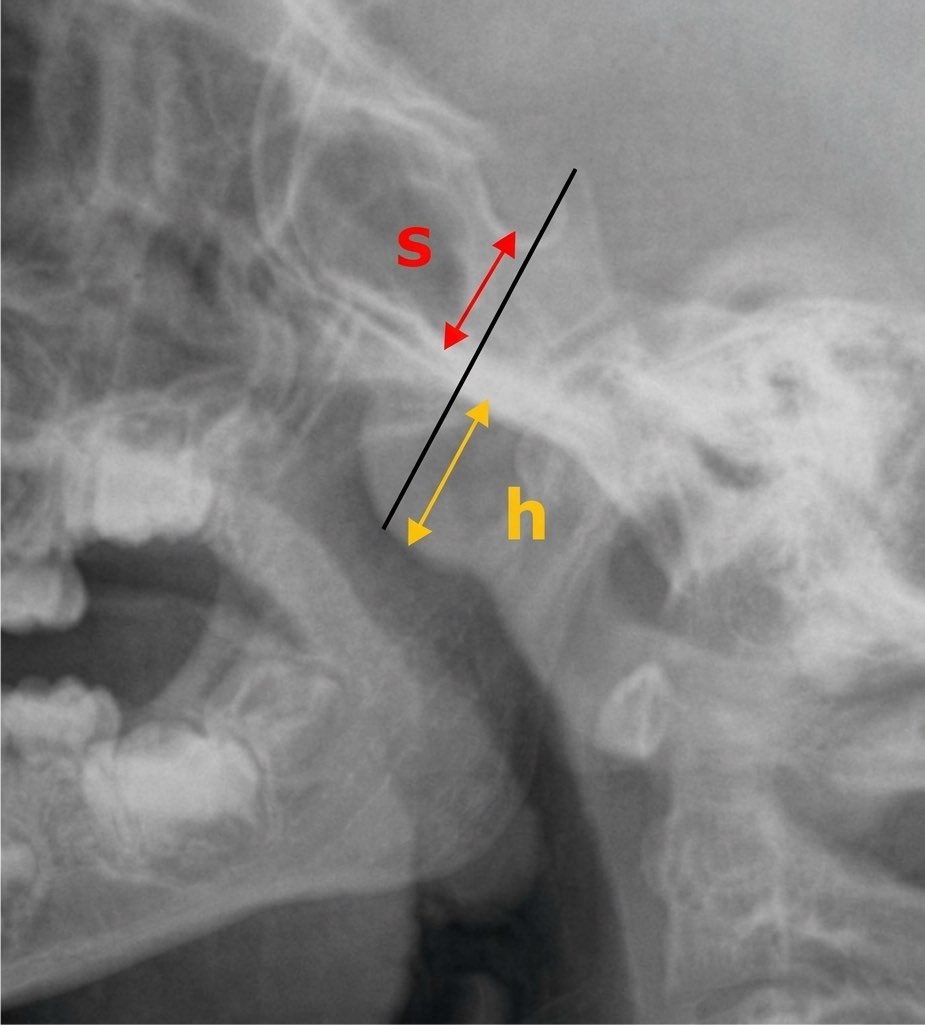

Bombement antérieur des parties molles du cavum.

Pas de retentissement significatif sur la filière naso-pharyngée.

Fente aérienne mesurant mm (norme > 5 mm).

Cadre osseux sans particularité.

hypertrophie végétations adénoïdes = h>s et fente < 5 mm